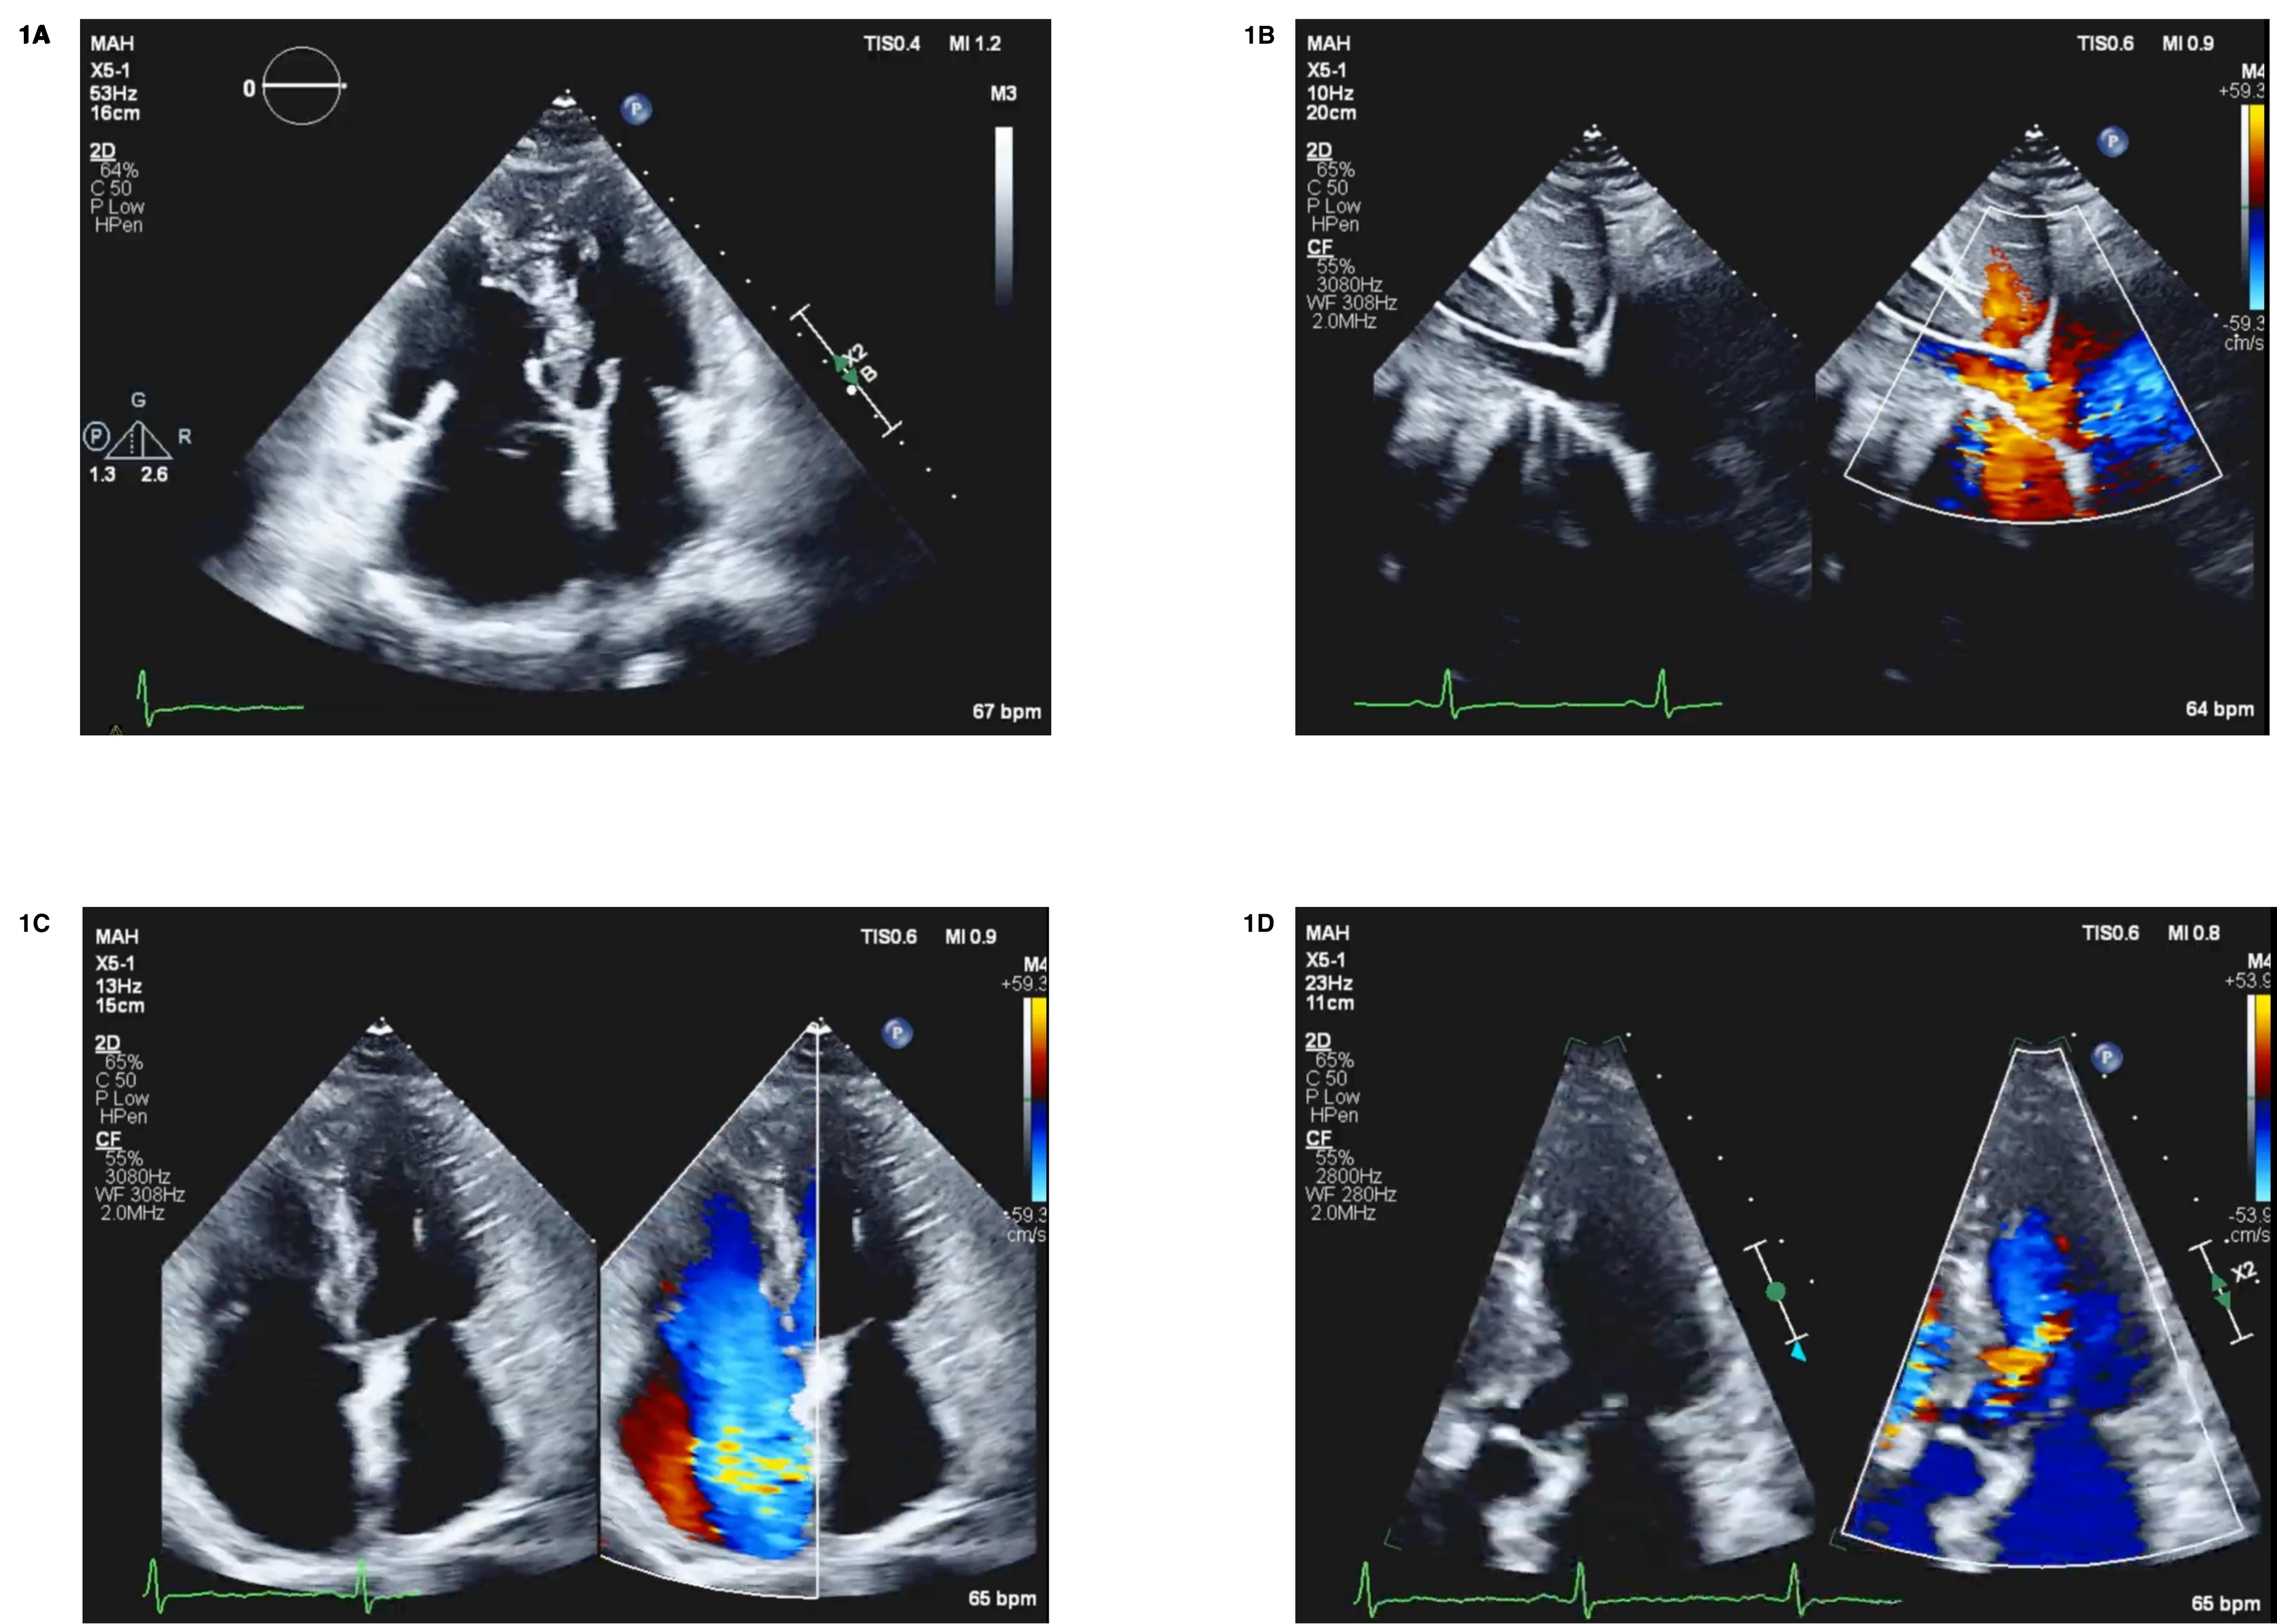

A 69-year-old female with worsening periorbital and bilateral leg edema was referred for cardiology evaluation. She also reported exertional dyspnea and orthopnea. She denied weight loss, abdominal pain, or diarrhea. Physical exam revealed a flushed appearance with a left sternal border holosystolic murmur. A transesophageal echocardiogram (TEE) showed LV ejection fraction 60%, asymmetric LV hypertrophy, severe tricuspid regurgitation (TR) with thickened and immobile leaflets, flow reversal in the IVC and hepatic veins, thickened pulmonic valve with moderate pulmonic insufficiency and a dagger-shaped Doppler profile, and moderate aortic regurgitation (Fig 1).

CHD is a serious manifestation of carcinoid syndrome, caused by serotonin-induced fibrous plaque deposition on tricuspid and pulmonic valves, leading to immobile leaflets and severe regurgitation. Primary ovarian NETs causing CHD are exceedingly rare, with only isolated case reports. Clinicians should suspect CHD in patients with right-sided heart failure, flushing, or characteristic echocardiographic findings—such as thickened valves and hepatic vein flow reversal—and confirm with elevated 5-HIAA levels.